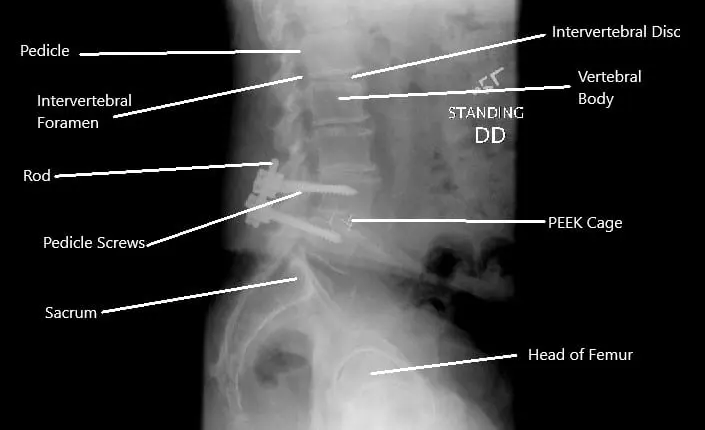

X-ray showing decompression and fusion of the L4-L5 vertebrae.

Surgical Care

Common surgical options include:

- Pars repair: Fixes small fractures in the pars interarticularis.

- Decompression (laminectomy): Removes tissue pressing on the nerves.

- Spinal fusion: Stabilizes the affected vertebrae using screws, rods, or bone grafts.